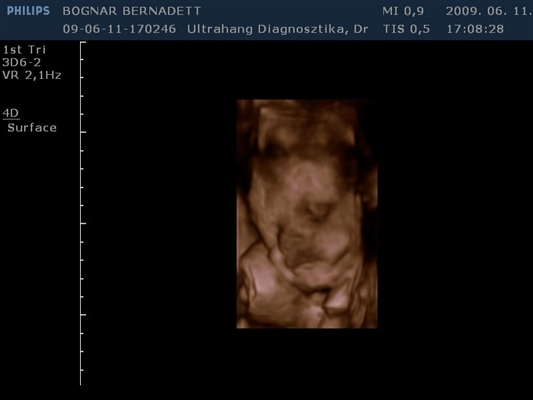

Kb. 3,5 hete én is voltam 4D-n és egy egész jó kis kép kerekedett belőle, majd felteszem.